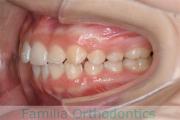

歯並びを治したいということで来院されました。下あごがやや右側に偏位して後退している、上顎前突(出っ歯)でした。上下左右から小臼歯を抜歯して、歯科矯正用アンカースクリューを併用したマルチブラケット法にて治療を行いました。約2年、24回の来院をしていただきました。

下顎の後退はいびきなどの上部気道の障害が出やすいと考えられます。

前歯の関係など

右側

正面

左側